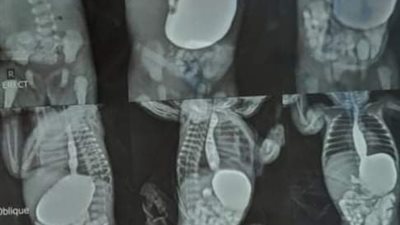

استخرج فريق طبي داخل مستشفى ملوي التخصصي جنوب محافظة المنيا، جسما صلبا من القصبة الهوائية لطفل يبلغ من العمر 6 سنوات كان يعاني من أعراض ما بعد استنشاق جسم غريب.

وأعلنت المستشفى، عن استقبال الفريق الطبي، الطفل داخل المستشفى، وإجراء منظار القصبة الهوائية، وجرى استخراج الجسم الصلب،. وتبيّن أنه "مسمار"، وتماثل الطفل للشفاء بعد إجراء اللازم واستخراج المسمار، وجرى حجزه تحت الملاحظة لمده 48 ساعه ثم غادر المستشفى لمحل إقامته بمحافظة سوهاج.

وأشرف على عملية استخراج المسمار، كلا من، الدكتور أحمد أنور العريبي، والدكتور محمد شوقي زهران استشاري جراحه القلب والصدر.

واستقبل قسم الطوارئ بالمستشفى، مريضا 22 سنة بادعاء سقوط على جسم صلب وبعد عمل الأشعة تبين وجود تجمع دموي ضخم بالناحية اليسرى من الصدر وتجمع دموي حول القلب.

وتم عمل استكشاف جراحي للصدر وتبين وجود نزيف شديد وتمت السيطرة علي مصدر النزيف داخل الصدر، وتمت الجراحة بنجاح بإشراف الأطباء محمد شوقي زهران استشاري جراحة القلب والصدر وعبد الرحمن حسن استشاري التخدير ونورا أبو الشلابي استشاري عناية مركزة وتمريض العمليات.